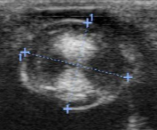

what features show this is a diabetic cataract?

Ultrasound is especially helpful

diabetic cataract has the hourglass appearance on ultrasound

what is the etiology/predisposition of lens subluxation/luxation?